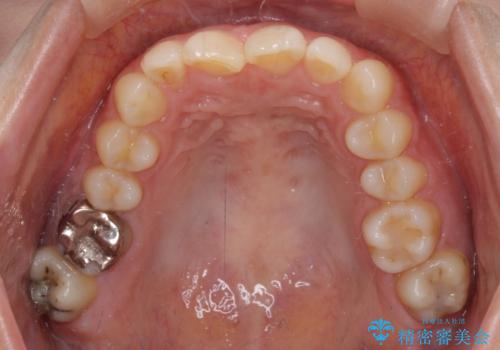

上下ともにデコボコの程度は著しいものではなく、インビザラインで十分に対応可能な歯列不正でした。

後戻りによりスペースができてしまうことを避ける目的で、IPR(歯と歯の間を削る)を極力用いない矯正治療を行うこととしました。